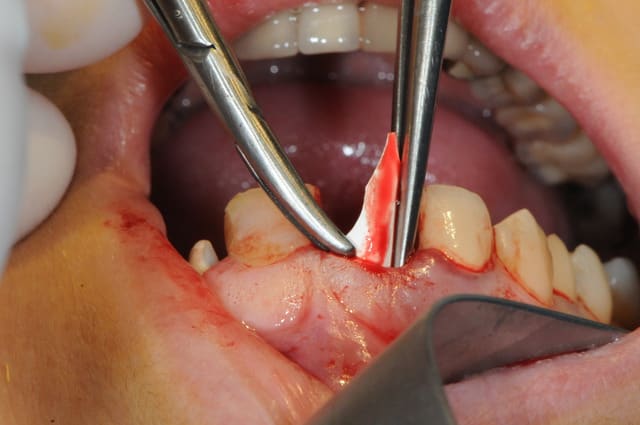

tu peux aussi faire ça;

glisser et interposer une membrane entre la parois vestibulaire osseuse et le périoste que tu décolles en partant de l'alvéole et en restant en contact osseux...